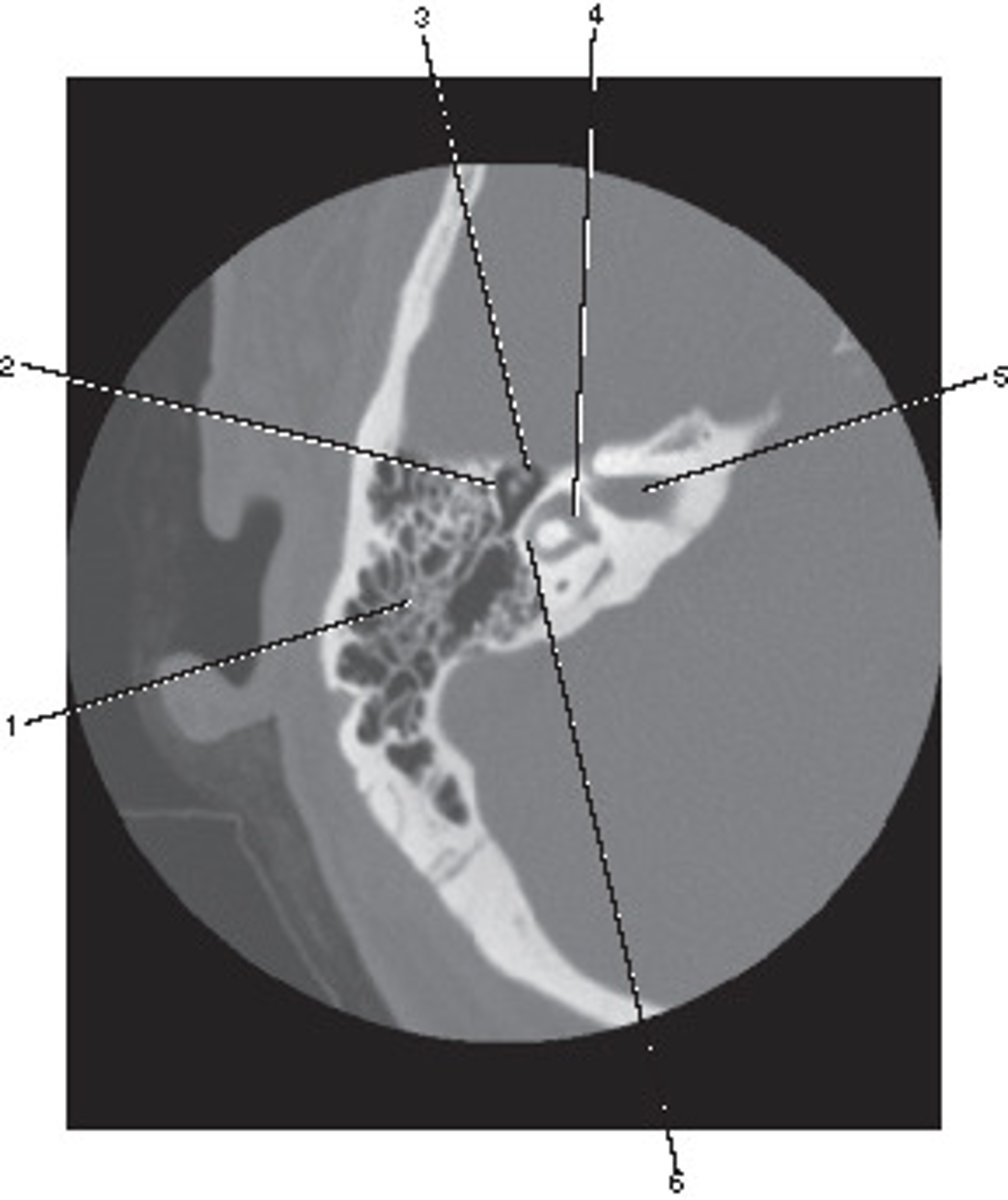

Internal Auditory Canal

Number 5 corresponds to which of the following?

<p>Number 5 corresponds to which of the following?</p>

External Auditory Meatus

Number 3 corresponds to which of the following?

<p>Number 3 corresponds to which of the following?</p>

Which number corresponds to the vestibule?

<p>Which number corresponds to the vestibule?</p>

Semicircular Canal

Number 4 corresponds to which of the following?

<p>Number 4 corresponds to which of the following?</p>

Number 2 corresponds to which of the following?

<p>Number 2 corresponds to which of the following?</p>